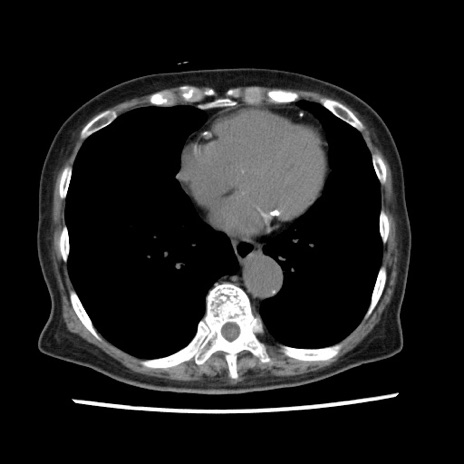

症例1(横断像)

【症例】80歳代女性

【主訴】腹痛

【現病歴】8時間前から腹痛あり来院。

【既往歴】糖尿病、脂質異常症、子宮体癌にて子宮全摘術

【身体所見】意識清明・会話良好だが腹痛で苦悶様、全腹部にわたって反跳痛と圧痛あり

【データ】WBC 13600、CRP 0.14、LDH 224、CK 90